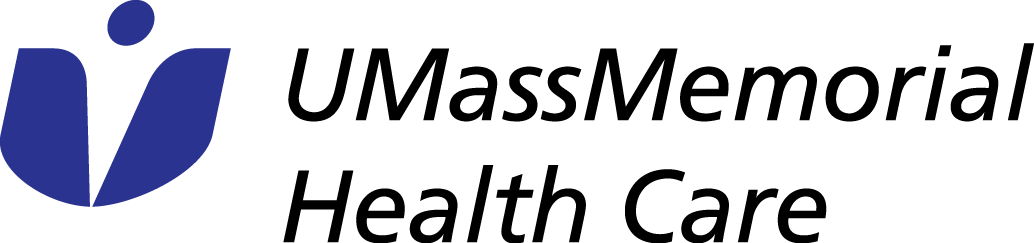

- Knee MRI current image quality, this sequence takes a little over 2 minutes to perform.

- Image quality is visibly degraded when the protocol is adjusted to decrease scan time to 1 minute using conventional methods.

- Image quality is sharper and less noisy when scan time is decreased to 1 minute and the images are reconstructed using the machine learning algorithm.

Data collected at Shields Framingham in collaboration with GE Healthcare.